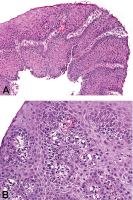

Abbildung 1a-b: (a) Regeneratorische Veränderungen des Plattenepithels des Ösophagus bei chronischem Reflux (hyperregeneratorische Ösophagopathie) mit Verbreiterung der Basalzelllagen und Verlängerung der Stromapapillen (original ×100). (b) Dilatation der Interzellularspalten und leichte entzündliche Infiltration (original ×200).